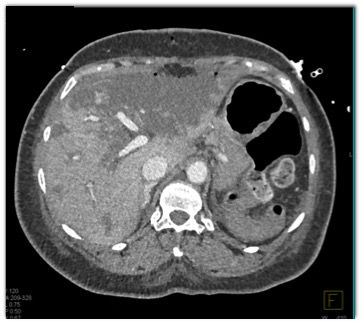

In this patient post recent Whipples procedure the best diagnosis is?

CTisus Quiz   CTisus Quiz

liver abscess

liver infarction

fatty infiltration of the liver

tumor recurrence in the liver